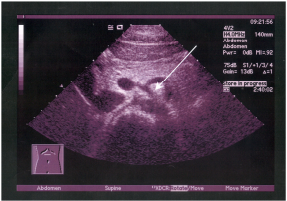

63 附圖為一成年男性之膀胱超音波圖,箭號所指為何? (A)輸尿管膨出(ureterocele) (B)移形細胞癌(C)血腫塊 (D)膀胱結石